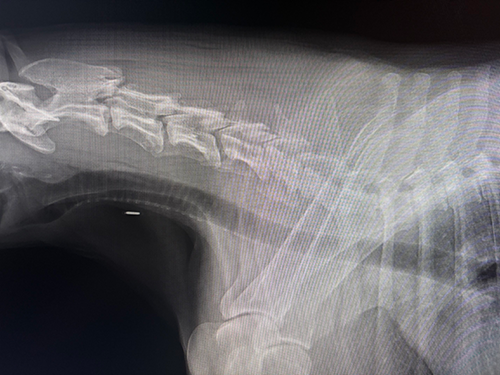

結果 頸椎に明らかに異常がでていた。

PLDDを受けるならできるだけ早めに。ただし年齢を考えると、PLDDをしたからと言って改善するとは断言できないとのこと。痛くなった時のためにフィロコックス錠だけもらって帰ってきた。